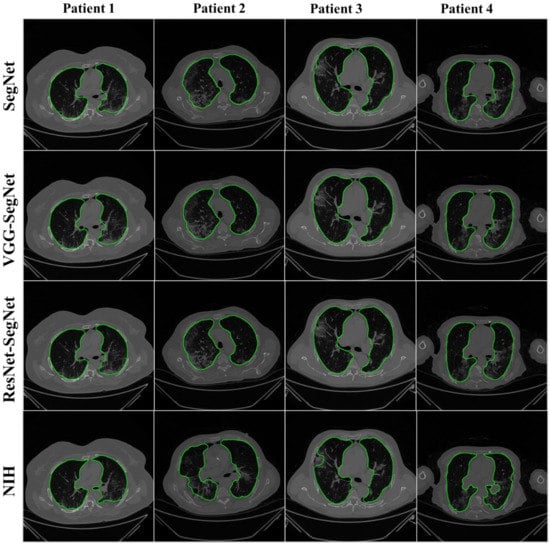

4.2.1. Visualization of Lung Boundary and Regional Lung Error